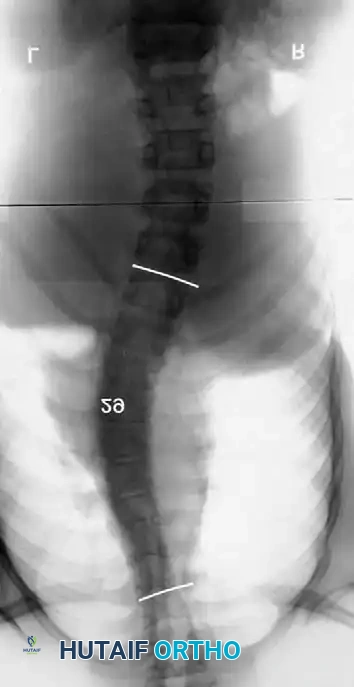

Associated Surgical & Radiographic Imaging

Hutaifortho's Orthopaedic Diagram

* Including the Pelvis: Mandatory for nonambulators with fixed spinopelvic obliquity. If bending or traction films reveal more than 10 to 15 degrees of L4 or L5 tilt relative to the interiliac crest line, the fusion must extend to the pelvis.

Image

Maintaining physiological lumbar lordosis is paramount in insensate patients fused to the pelvis. Proper sagittal alignment distributes body weight equally beneath the ischial tuberosities and posterior thighs, drastically reducing the risk of pressure sores over the coccyx and sacrum.